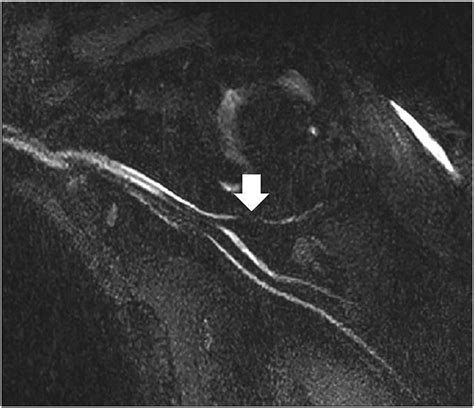

To overcome this, this specialized imaging employs specific pulse sequences designed to suppress the signal from fat—which often obscures nerve detail—while enhancing the signal from water-rich tissues like nerves. This process effectively makes the nerves "light up" on the resulting images, allowing radiologists to assess their anatomy, signal intensity, and trajectory in high detail.

Once the images are acquired, they are analyzed by a radiologist with specialized expertise in musculoskeletal or neuroradiology. The goal is to identify changes in the nerve's appearance. For instance, a healthy nerve typically appears as a thin, uniform structure with a consistent signal. In contrast, an injured or compressed nerve may exhibit:

• Increased signal intensity: Often indicative of edema (swelling) or inflammation within the nerve.

• Nerve enlargement (fascicular thickening): A sign that the nerve is being subjected to chronic pressure or trauma.